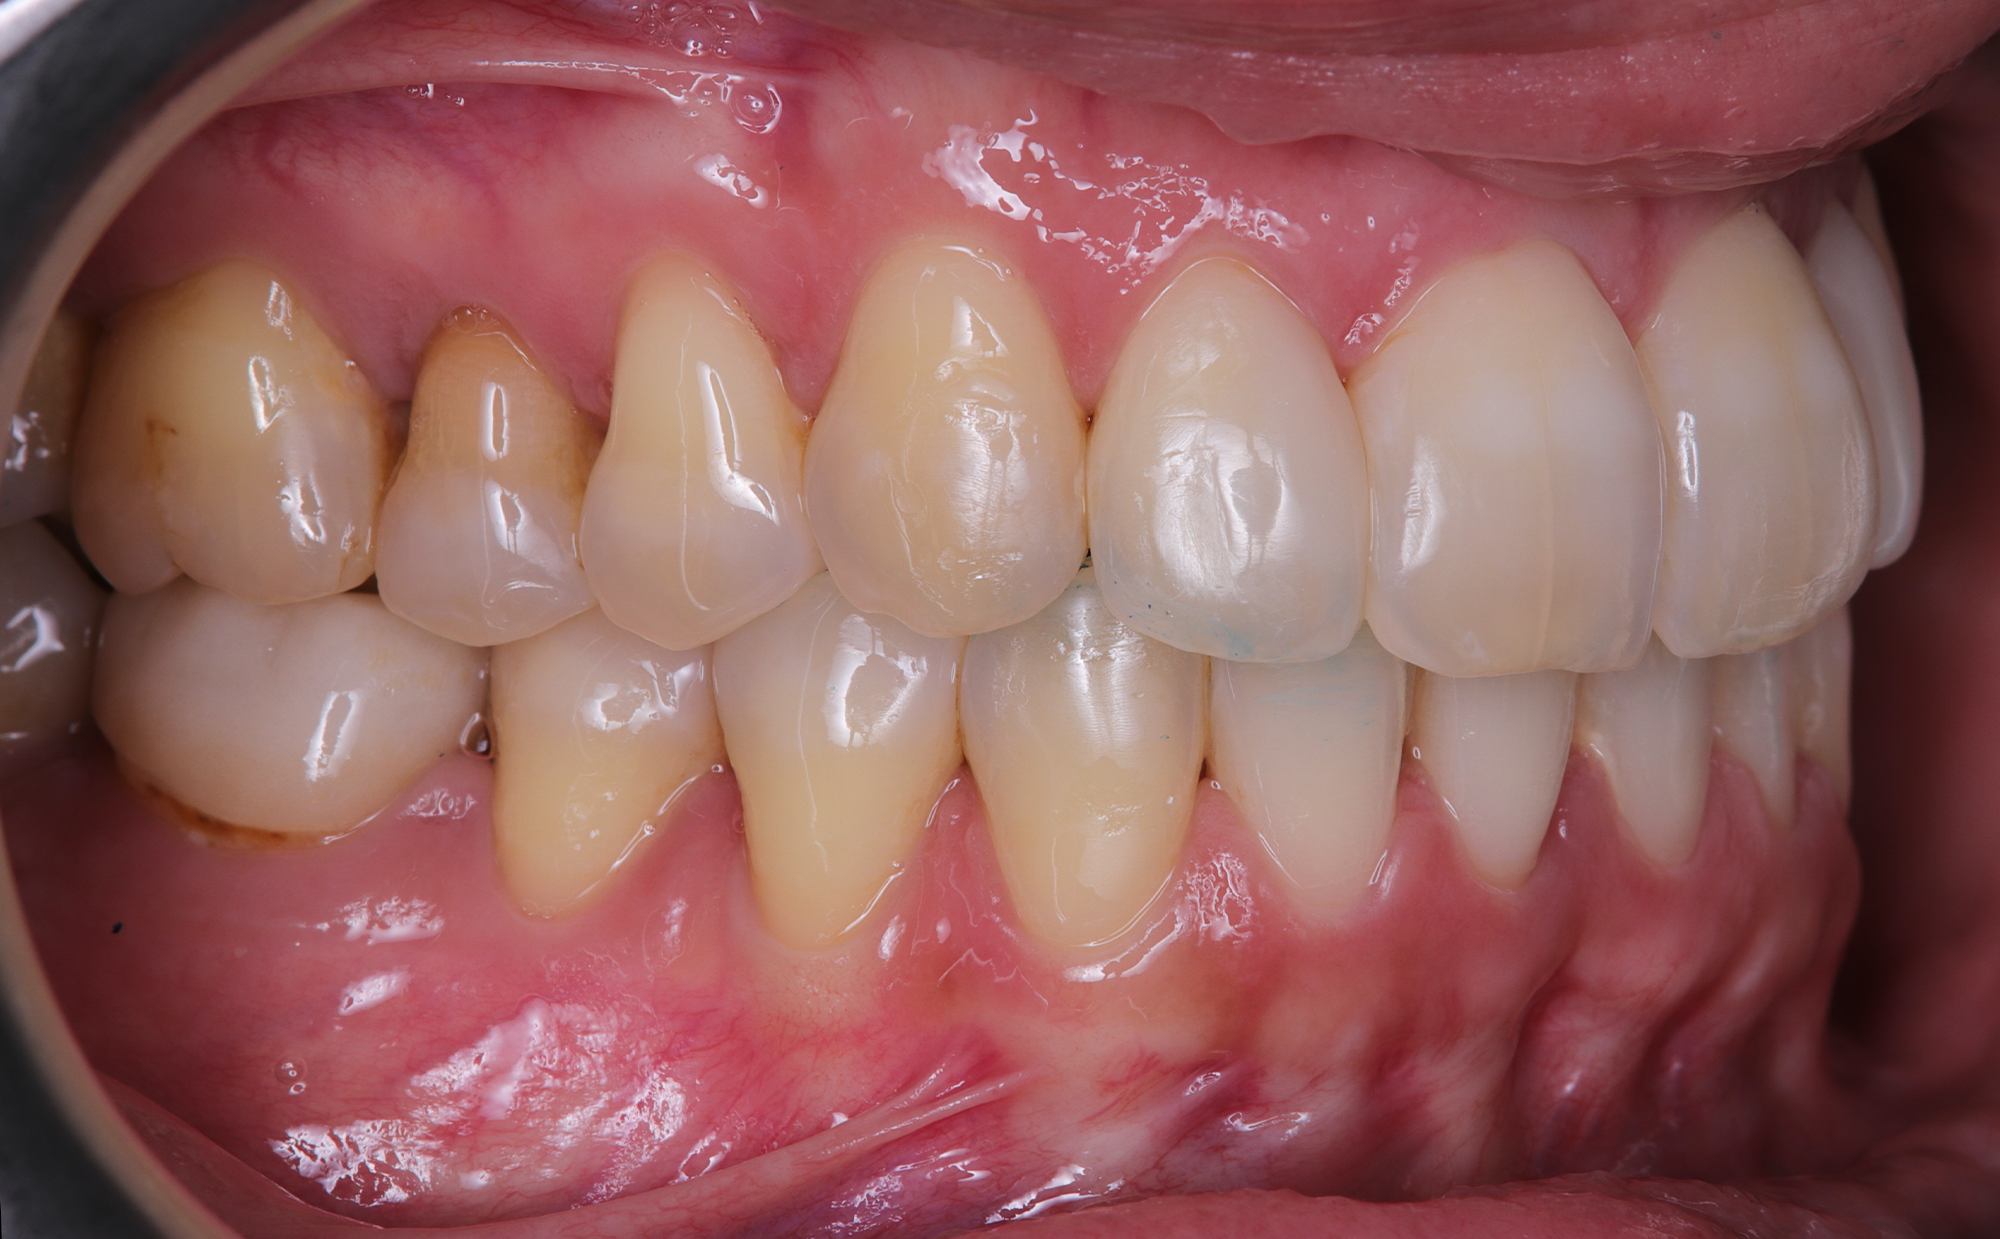

The patient, having completed a periodontal treatment phase, presented with significant aesthetic and functional concerns due to moderate crowding in both arches and a pronounced anterior crossbite. Clinical examination confirmed the need for comprehensive realignment, particularly in the anterior region. Although the patient had a history of periodontal issues, radiographic evaluation showed no signs of active disease. Based on these findings, the treatment plan was designed to carefully modulate orthodontic forces to protect the occlusion and surrounding tissues while addressing the misalignment.

To correct the misalignment and anterior crossbite without compromising tissue stability, a slower orthodontic treatment plan was devised using the Spark Advanced clear aligner system. The initial phase involved 36 aligners designed to gently expand and realign the dental arches, limiting the rate of tooth movement. Strategic interproximal reduction (IPR) was performed in the anterosuperior region (between teeth #21 and #11) to create the necessary space for proper alignment while avoiding excessive loading on the tissues.

To refine the results and enhance aesthetics, a second phase incorporating an additional 17 aligners was introduced. During this refinement stage, careful IPR in the lower arch helped harmonize the midline and achieve a balanced occlusion. Once satisfactory alignment was reached, provisional composite restorations were placed on the upper lateral incisors to aesthetically close any interproximal gaps.

A crucial aspect of the treatment was reducing the speed of tooth movement by 50%. This approach allowed a gradual application of orthodontic forces, giving the occlusion and tissues ample time to stabilize following the periodontal phase while effectively addressing the crowding and anterior crossbite.

At the conclusion of the treatment, the patient achieved excellent dental alignment and a stable occlusal relationship, particularly in the anterior region. Radiographs and clinical assessments confirmed that there was no further bone loss and that previous improvements were maintained. The aesthetic enhancement from the composite restorations further contributed to the overall success of the treatment.